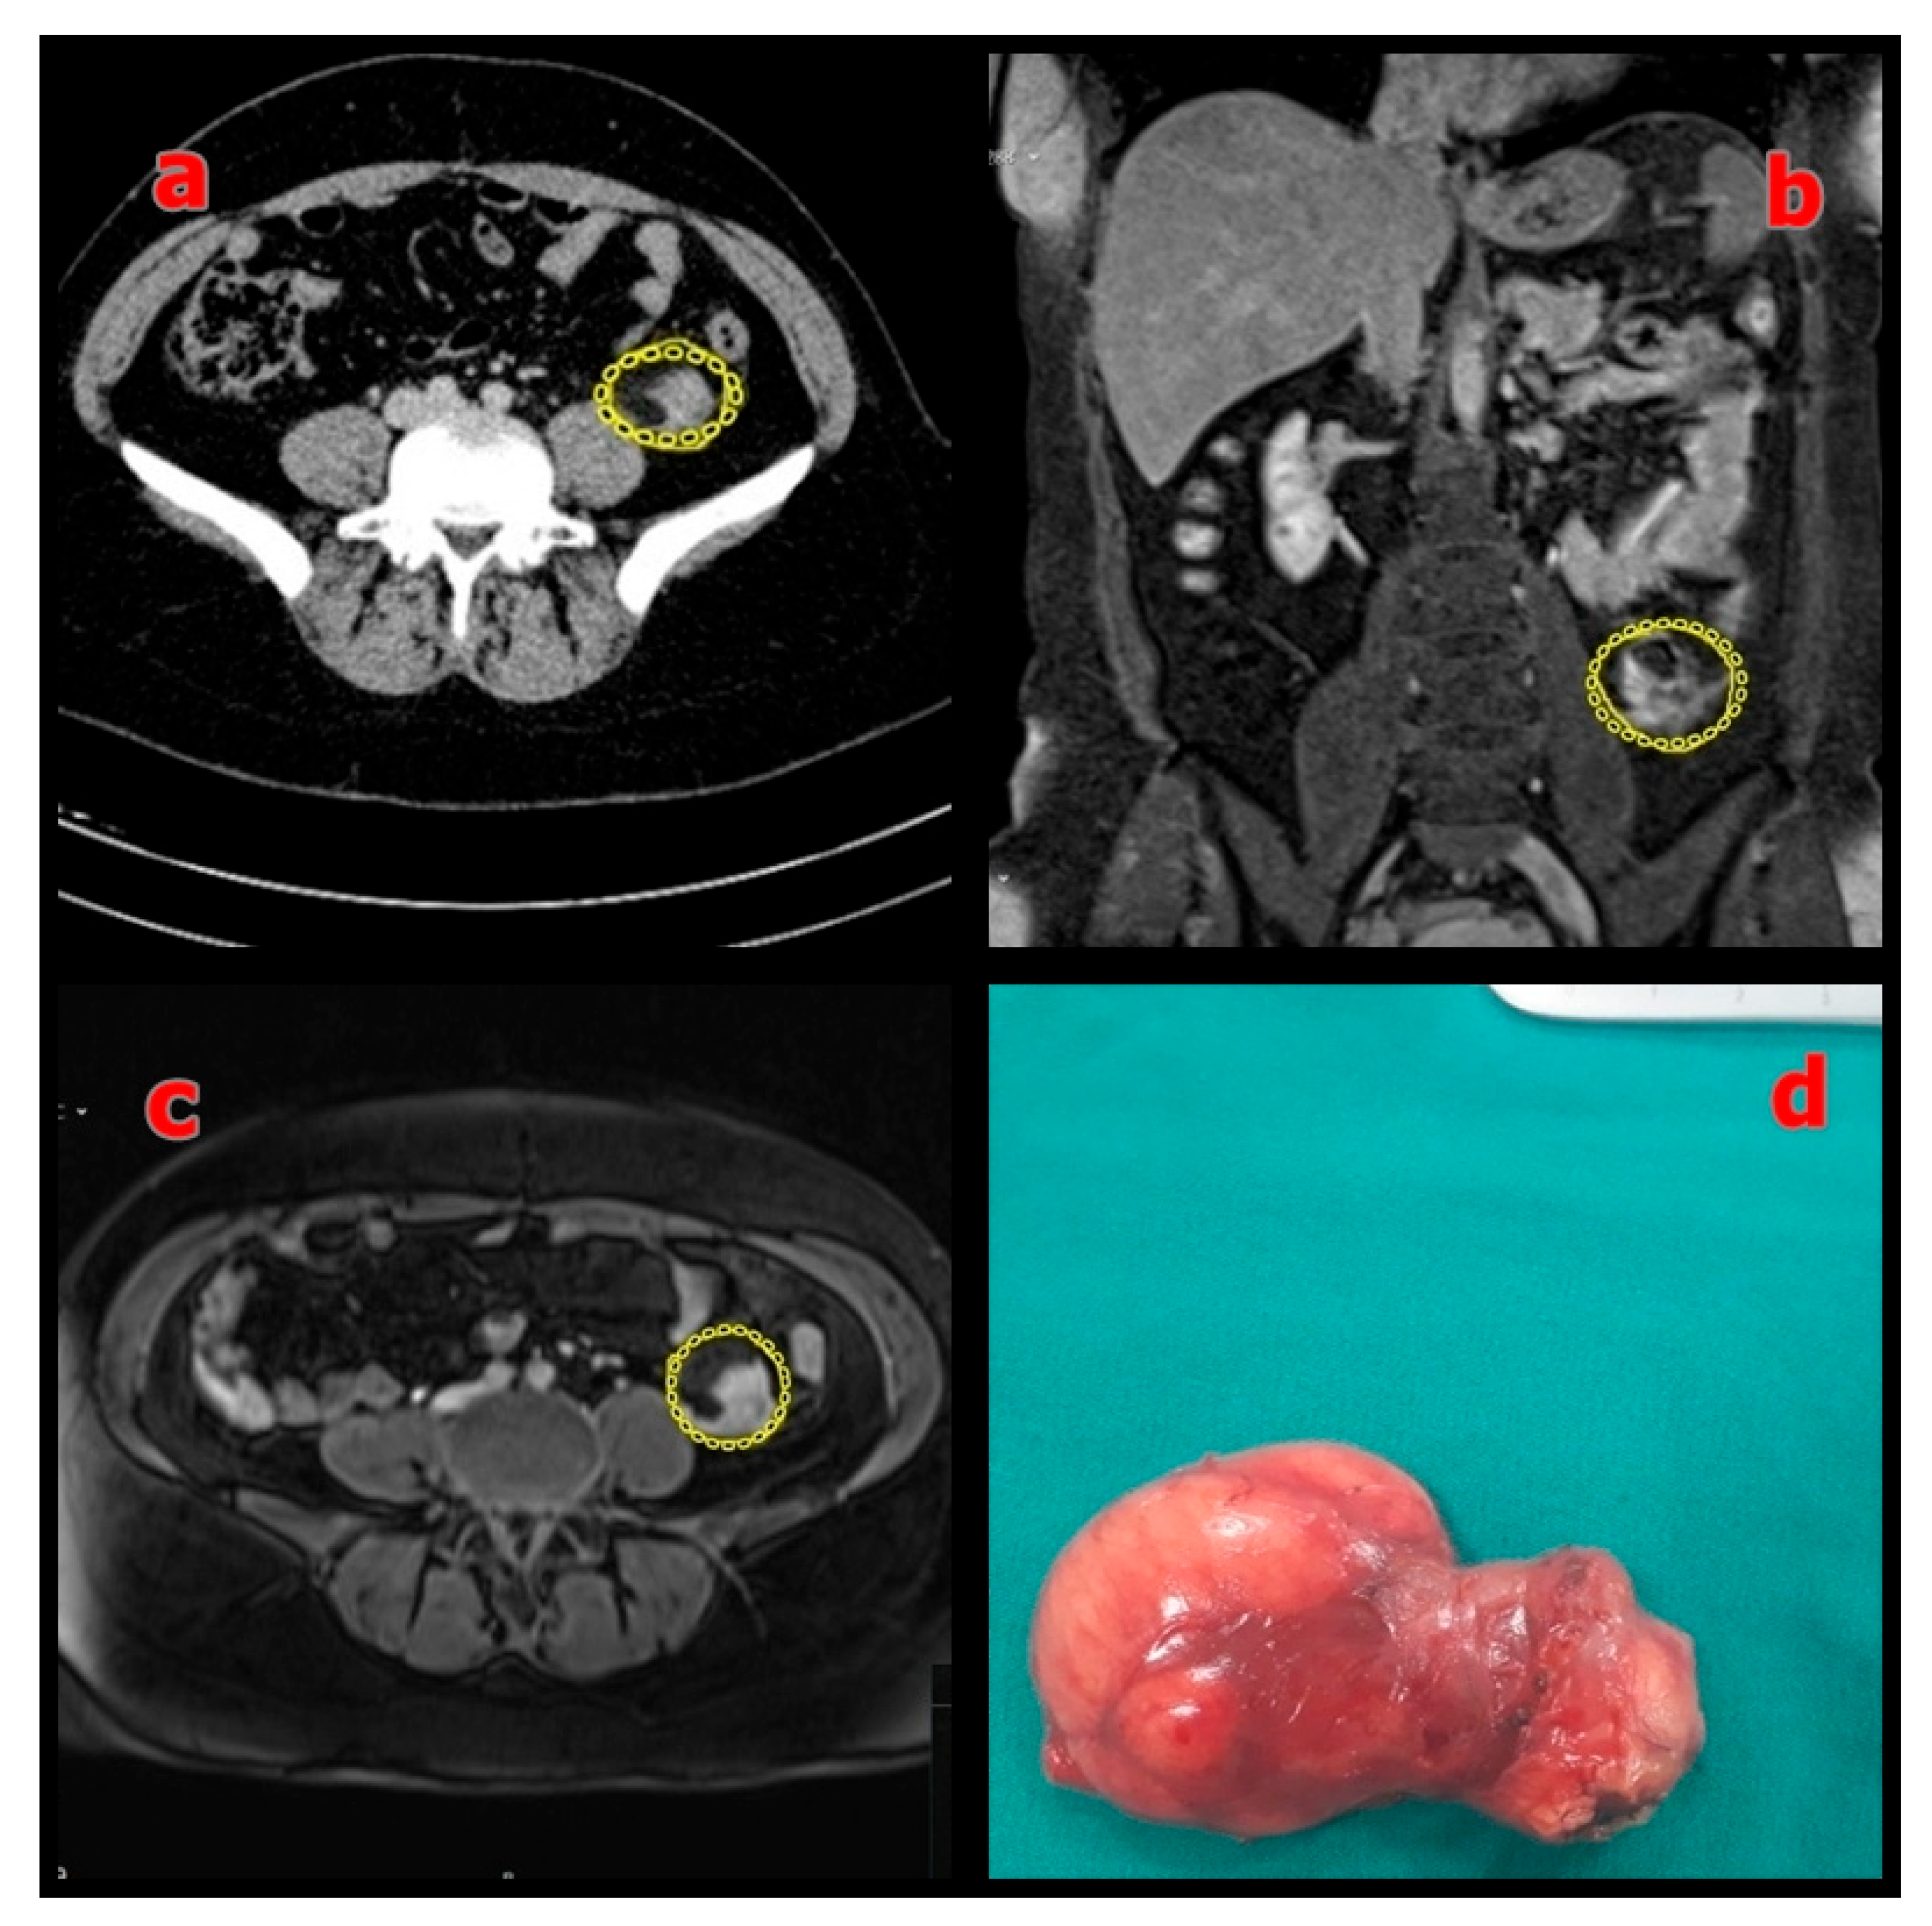

| Patient 7 | 43 | F | Left colon | Myxoid Liposarcoma | 12 × 11 × 2 | RT-CT | Yes | Alive | 117.2 |

| Patient 10 | 40 | M | Left Lower Quadrant | Myxoid Liposarcoma | 17 × 14 × 11.5 | No | No | Alive | 71.8 |